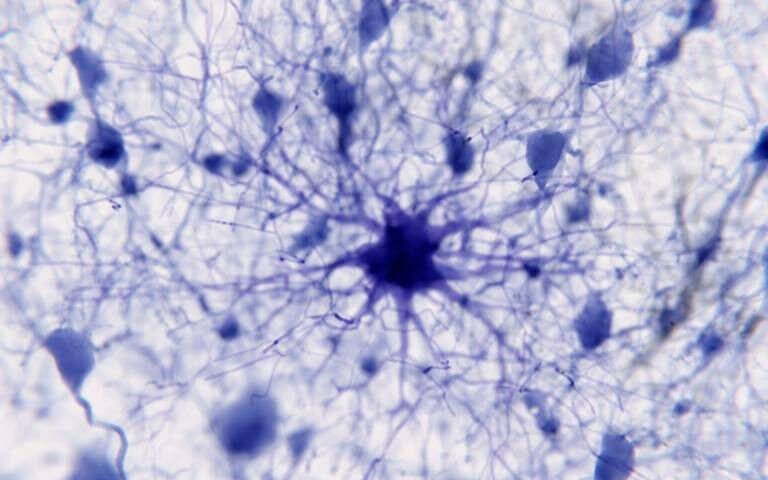

Protoplasmic astrocytes play an active role in neuronal communication through synapses and regulation of neural circuit function.

Protoplasmic astrocytes play an active role in neuronal communication through synapses and regulation of neural circuit function. Biotech company AstronauTx, aiming to develop novel treatments for Alzheimer's disease and other neurodegenerative disorders, has closed a £48m ($61m) Series A financing. The company was launched in 2019 and spun out from UCL Business (UCLB), the commercialisation company for UCL, initially building on research from the Alzheimer's Research UK UCL Drug Discovery Institute (UCL DDI). The UCL DDI is positioned to couple the deep disease knowledge and biology expertise of the academic community at UCL and further afield with industry-standard drug discovery approaches, to rapidly translate emerging innovations into new medicines. AstronauTx and the UCL DDI have an ongoing drug discovery collaboration to develop new medicines that reset the behaviour of astrocytes, crucial support cells in the brain. Astrocytes are normally very important for keeping nerve cells functioning well, but they change in Alzheimer's disease and instead become damaging. Professor Paul Whiting (UCL Queen Square Institute of Neurology) is among the company's co-founders.